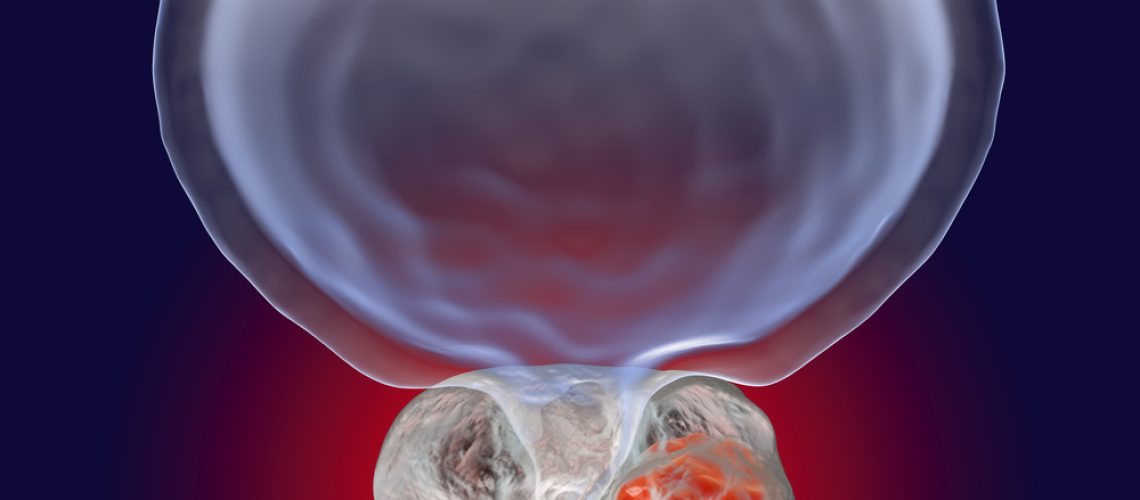

Processo cirúrgico para tratamento de câncer de próstata

A prostatectomia radical é o principal tipo de cirurgia aplicada para esse câncer. Por meio desse método, o médico cirurgião efetua a retirada de toda a próstata e de alguns tecidos ao seu redor, o que inclui as vesículas seminais. Essa operação pode ser feita de várias maneiras diferentes. Pode ser realizada de forma menos invasiva, como por exemplo no caso das vias laparoscópica e robótica. Nessa situação, cortes minúsculos são feitos no abdômen para que seja possível inserir uma câmera e os instrumentos cirúrgicos necessários para a realização do procedimento. Mas também pode seguir o padrão tradicional, isto é, por meio de um corte feito no períneo ou na região inferior do abdômen. Entretanto, quanto a resultados efetivos, preservação da continência urinária, da potência sexual e de possibilidade de cura, ambas as formas do procedimento se assemelham. Em todos os casos, depois de feita a retirada da próstata, o médico sutura a bexiga na uretra, definindo, assim, um caminho para a urina. Em quase que todos os procedimentos o homem pode voltar a comer normalmente no primeiro dia. Com relação à sonda, ela permanece por um período que pode variar entre sete e dez dias. No entanto, o indivíduo recebe alta do hospital bem antes disso, caso nenhuma complicação tenha sido verificada.Riscos da cirurgia